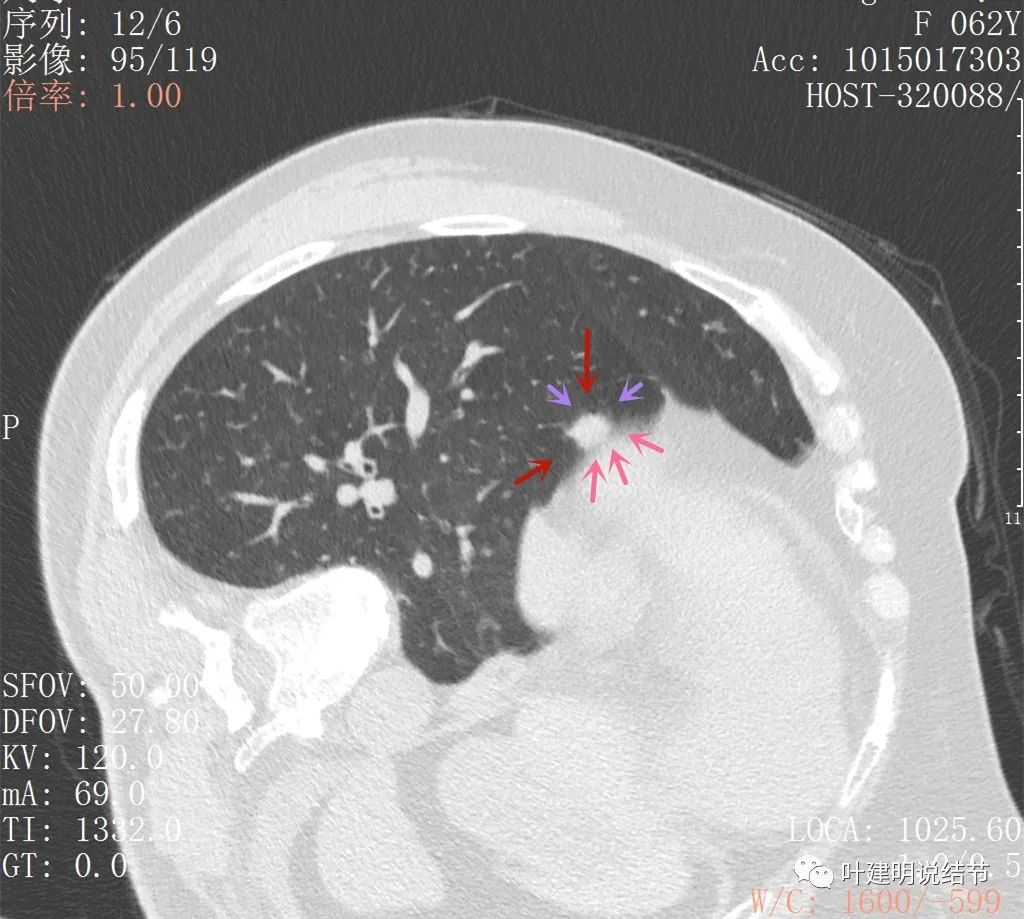

上图粉色箭头示与膈肌间的缝隙,紫色箭头示病灶有细毛刺征,红色箭头示病灶实性密度

上图见病灶较为典型的恶性征象,边缘有细毛刺,也有少许磨玻璃(绿色所指),还有血管进入(桔色),总体上看,像颗杨梅